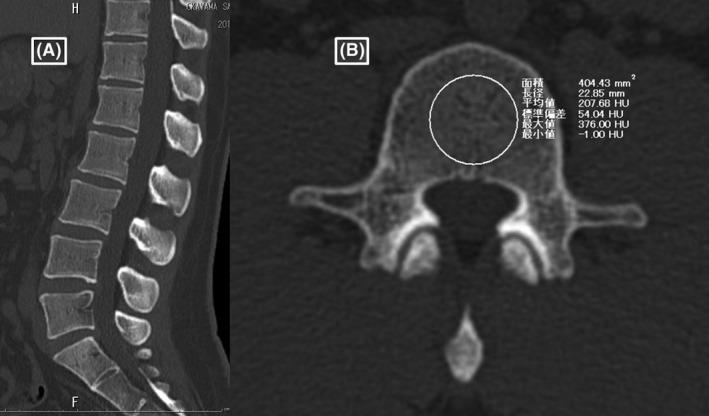

METHODS

A single-center, retrospective, observational study was undertaken to evaluate BMD after critical care at Okayama Saiseikai General Hospital (Okayama, Japan) from January 2016 to April 2018. Sepsis was defined as an absolute increase of ≥2 in Sequential Organ Failure Assessment score in the intensive care unit or high care unit. Bone mineral density was evaluated in Hounsfield units (HU) by computed tomography. Patients were divided into groups based on the presence or absence of osteoporosis, which was defined as average vertebral body HU <110. Paired -tests were used to compare the mean BMD of each vertebra between before and after critical care. We also analyzed accidental bone fracture events after discharge. The survival rate was analyzed as an outcome using the Kaplan-Meier method.

使用腹部计算机断层扫描检查脓毒症治疗患者的椎骨骨密度(BMD)变化。

方法

进行了一项单中心、回顾性观察研究,以评估2016年1月至2018年4月在冈山西条综合医院(日本冈山)接受重症监护后的骨密度。脓毒症定义为重症监护病房或高级护理病房中序贯器官衰竭评估评分绝对增加≥2。通过计算机断层扫描以亨氏单位(HU)评估骨密度。根据是否存在骨质疏松症将患者分组,骨质疏松症定义为平均椎体HU<110。使用配对t检验比较重症监护前后每个椎骨的平均骨密度。我们还分析了出院后的意外骨折事件。使用Kaplan-Meier方法分析生存率作为结果。